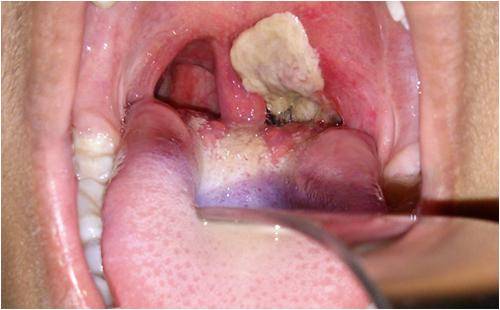

白喉是由白喉棒状杆菌(Corynebacterium Diphtheriae)引起的一种感染。通常在发生暴露后2至5天出现症状和体征,其严重程度为轻度到重度不等。症状的出现通常较为缓慢,初始症状为咽喉痛和发热。严重情况下,细菌会产生一种毒物(毒素),在咽喉后部形成厚厚的灰色或白色斑块。这会阻塞呼吸道,导致呼吸或吞咽困难,并出现犬吠样咳。颈部可能在一定程度上由于淋巴结肿大而出现肿胀。

白喉的临床诊断通常依赖于覆蓋咽部的灰色渗出物(假膜)。虽然建议对疑似病例开展实验室检查,以达到确诊目的,但应立即启动治疗。